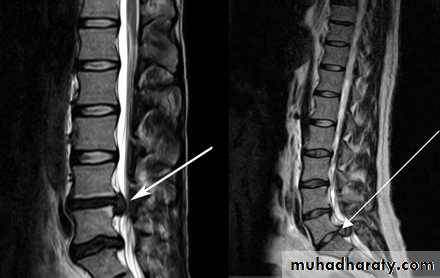

• Incomplete• Cauda Equina syndrome:

• # Saddle anesthesia, urinary retention and stool incontinence.

• # Usually due to large central disc herniation rather than fracture.

• Nerve root deficit: LMN

Cauda Equina Syndrome

A surgical emergency.Requires full neurologic examination including rectal examination for anal tone.

Investigations: X-rays initially, but MRI is mandatory as X-rays are usually unremarkable.

Treatment: Emergency decompression-usually discectomy and wide laminectomy within 24 hours.